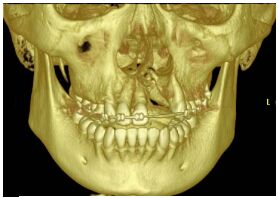

76.患者為 18 歲男性,從 3D CT scan 影像(如下圖)所呈現,其臨床診斷最可能為下列何者?(A) 囊腫(cyst) (B) 齒槽骨裂(alveolar cleft) (C) 纖維瘤(fibroma) (D) 造釉細胞瘤(ameloblastoma)